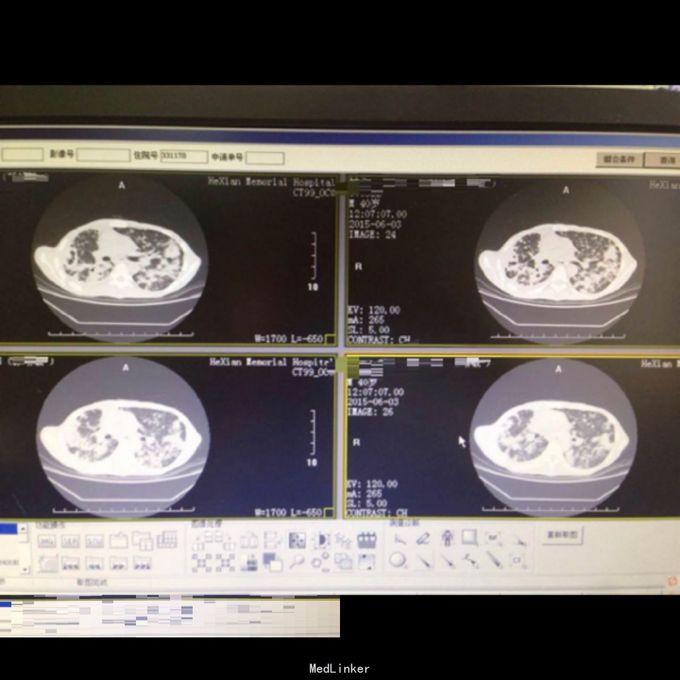

体查:T:36.9℃ R: 23次/分 P:86次/分 BP:130/70mmHg,消瘦,自主体位,神志清楚,对答切题,查体合作。皮肤粘膜未见苍白、黄染,未见皮疹,无皮下出血点,无伤口。全身浅表淋巴结未扪及肿大。口唇红润,伸舌居中,咽部无充血,扁桃体无肿大。颈软,无抵抗,颈静脉无充盈,肝颈静脉回流征(-),气管居中,胸廓对称无畸形、无局部膨隆或凹陷。呼吸平稳,节律规则。双侧呼吸动度对称。双肺部叩诊清音。双肺呼吸音清,双肺未闻及干湿性啰音。心界不大,心率86次/分,律齐,各瓣膜区未闻及病理性杂音。 辅助检查: 双肺CT:1、双肺弥漫性病变,考虑继发型结核,并双肺上叶、下叶背段多发空洞形成、支气管扩张,建议治疗后复查。2、双侧胸膜增厚、粘连,右侧少量胸腔积液。